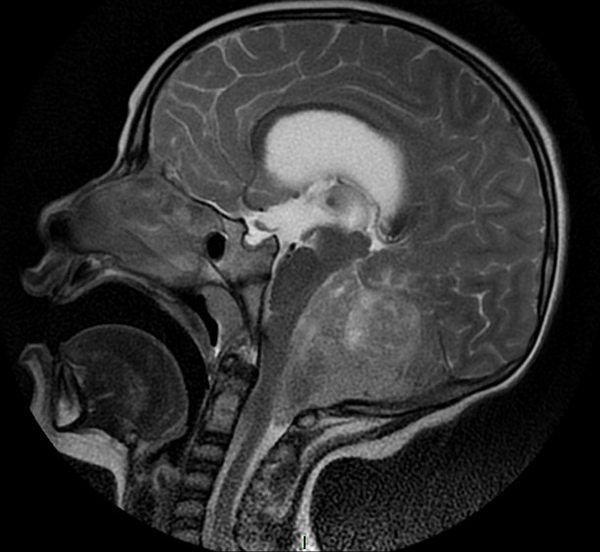

En resonancia magnética (RM) de cerebro se observa tumoración heterogénea sólida o sólido-quística con áreas de hemorragia, quistes y calcificaciones, que capta contraste en forma variable. (Fig. 1, 2, 3, 4). El patrón en espectroscopía se caracteriza por presentar pico de Colina (Cho) y descenso de N-Acetilaspartato (NAA).

Fig 2:

RM corte sagital, secuencia T1 con contraste. Se observa neoformación medial, solido-quística, heterogénea de bordes irregulares en la topografía del VI ventrículo que ocupa la totalidad del mismo, que realza en forma heterogénea tras la administración del contraste y se proyecta caudalmente a través del foramen magno. Se evidencia colapso del VI ventrículo, desplazamiento del tronco cerebral hacia anterior y abombamiento del cuerpo calloso debido a la hidrocefalia obstructiva.